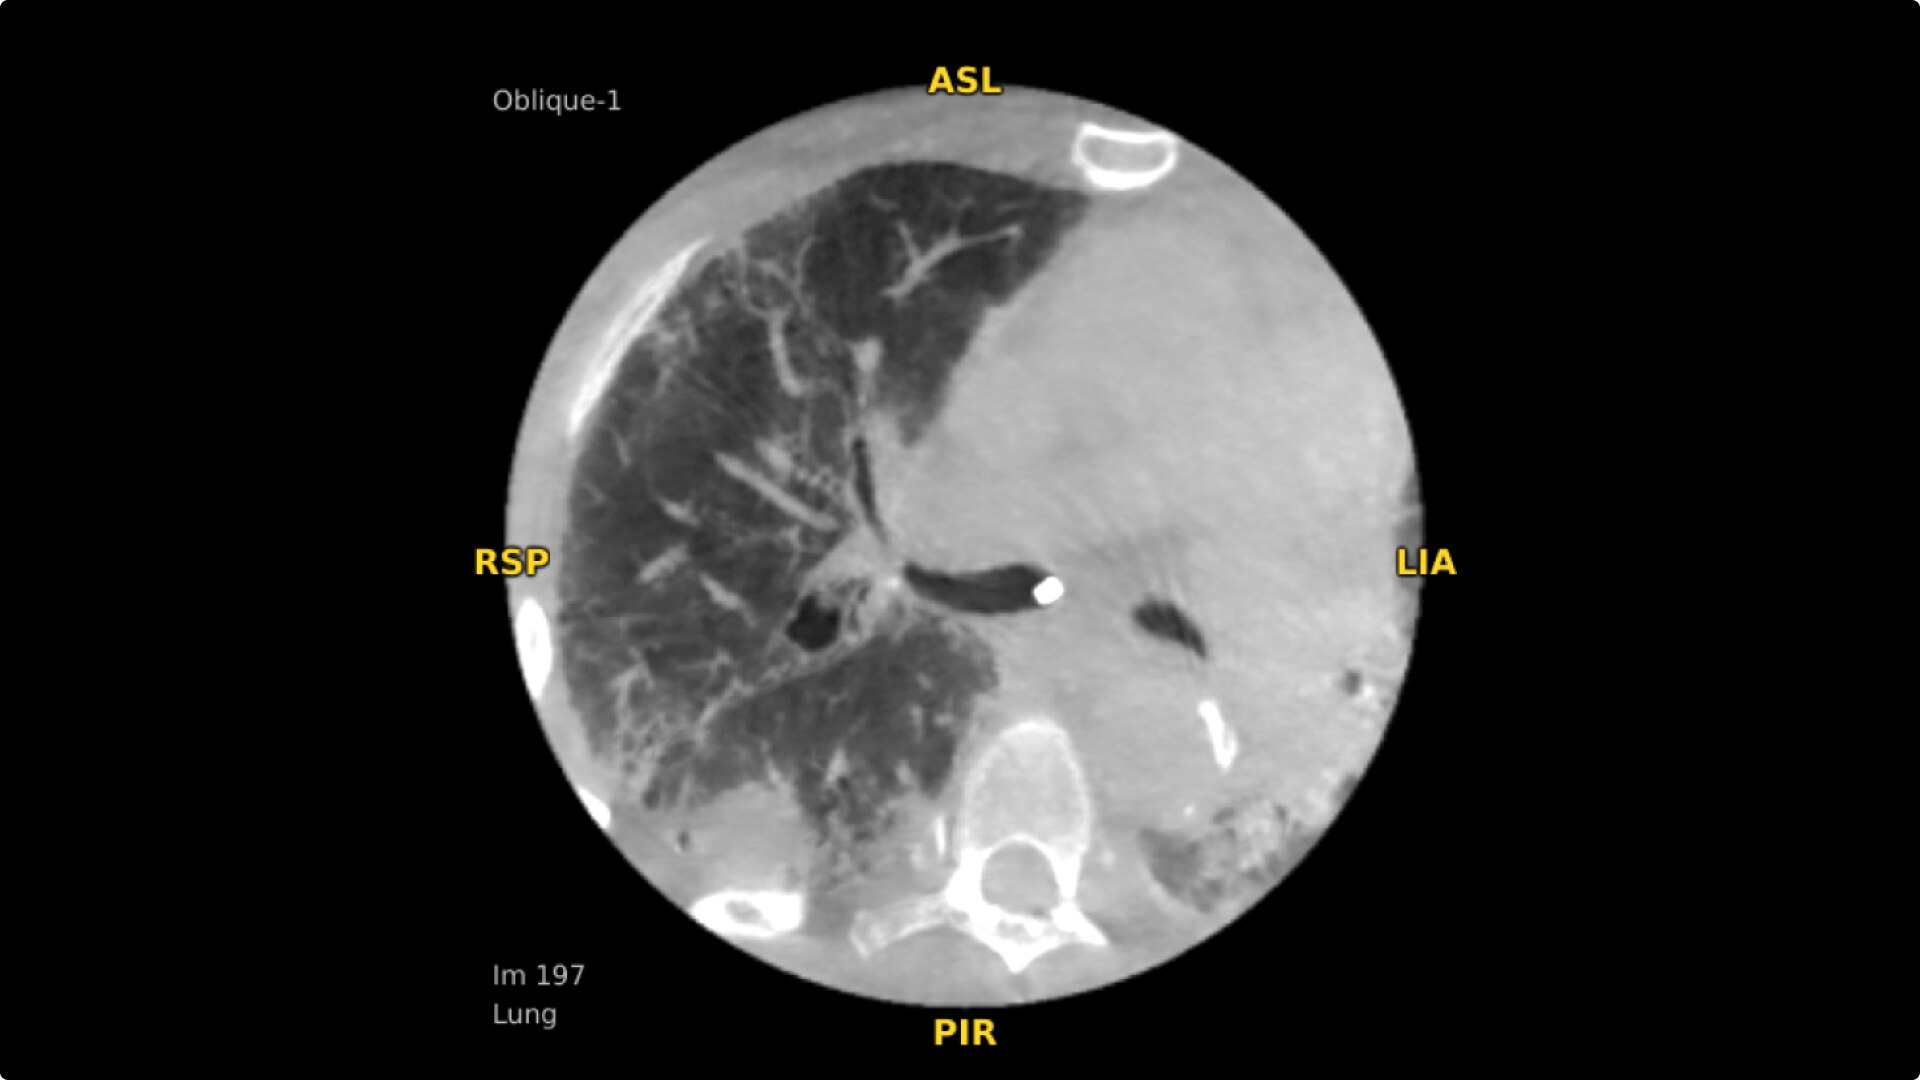

Select Lung Preset for optimized view of pulmonary structures. Easily change slices or adjust slice thickness for multiplanar assessment of lesions and bronchial structures.

Analyze CT-like images with the OEC 3D Volume Viewer which includes Multi Oblique Mode with reference coordinates, Window Level/Window Width, rotate, zoom, and more for quick and comprehensive tool-in-lesion confirmation.